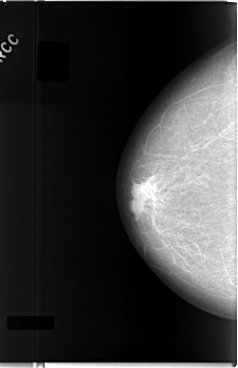

C_0027_1.RIGHT_MLO

RIGHT_CC LINES 5888 PIXELS_PER_LINE 3808 BITS_PER_PIXEL 12 RESOLUTION 50 NON_OVERLAY

RIGHT_MLO LINES 5768 PIXELS_PER_LINE 3504 BITS_PER_PIXEL 12 RESOLUTION 50 NON_OVERLAY